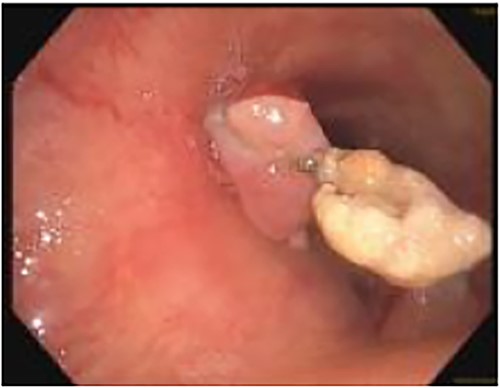

This was the first clear evidence of esophagotracheal communication. Laser debridement was successfully performed again in November 2022, leaving only a small portion where the stent eroded the trachea. On post-bronchoscopy Day 3, the patient reported significant improvements in breathing and energy. Over 6 months, she underwent laser debulking of the tracheal mass twice to manage tumor ingrowth (January and April 2023). Debridement was performed each time using a neodymium-yttrium-aluminum-garnet laser (Fig. 4). Between 380 and 560 joules were delivered to cauterize and debulk the invading tumor. The patient continues to be followed for palliative tumor debulking for ongoing symptom management.

Bronchoscopic view of the endobronchial obstruction. Invasion of the esophageal malignancy can be seen, as well as erosion of the esophageal stent into the lumen of the trachea.